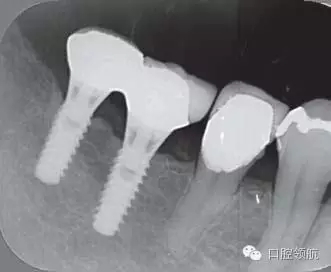

2005年4月時(shí),可見(左下第6顆牙) 部的種植體達(dá)到第4螺紋,(左下第7顆牙)的種植體周圍觀察到位于第3螺紋的頸部進(jìn)行性骨吸收(圖4)。到2009年9月時(shí),骨吸收像的周圍有了明顯的骨密度增加影像(圖5)。

圖4 (左下第6顆牙)的種植體達(dá)到第4螺紋, 7 的種植體達(dá)到第3螺紋的頸部進(jìn)行性骨吸收現(xiàn)象(2005年4月)。

圖5 骨吸收像的周圍有了明顯的骨密度增高影像(2009年9月)